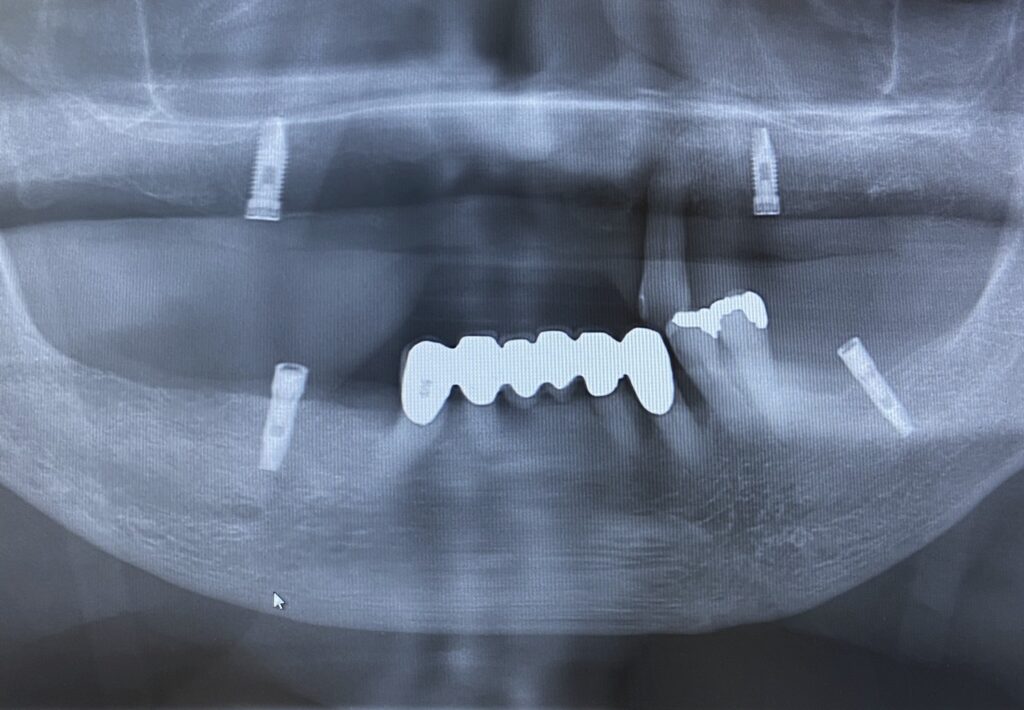

〇上顎のインプラントのデメリット

上顎のインプラントに見られるデメリットをご紹介します。

●上顎洞への穿孔

上顎洞とは、鼻の隣・目の下に位置する骨の空洞です。

上顎洞の真下に上顎の骨と奥歯があります。

歯が抜けると骨が減り、上顎の骨の厚みも薄くなります。

骨の厚みがかなり薄くなった場合、インプラントを埋め込むために骨に穴を開ける際、上顎洞に届く穴が抜けてしまう可能性があります。

●上顎洞へのインプラントの迷入

上顎洞の底の骨が薄くなっている場合、インプラントを埋め込む際に、インプラントが骨を突き抜けて、上顎洞の中に落ち込んでしまうことがあります。

〇下顎のインプラントのデメリット

続いて下顎のインプラントのデメリットについて解説します。

●下顎神経障害

下顎の奥歯の下に下顎管という神経や動脈が通っている骨のトンネルがあります。

インプラントを埋め込むために穴を開けますが、このとき下顎管を傷つけてしまうと、そこを通っている神経が傷つくことがあります。

すると、下唇や顎先の感覚が鈍くなってしまうリスクがあります。

●骨造成手術

下顎の場合も、骨の厚みが足りない場合は、骨の厚みを回復させなければなりません。

下顎に対しては、ご自身の他の部分の骨や人工骨材料を埋め込み、メンブレンという膜やチタン性のメッシュで囲うGBRという骨造成手術などが選ばれます。

移植骨が安定化しなければ、骨の厚みを得ることはできず、インプラント治療が困難になるデメリットがあります。